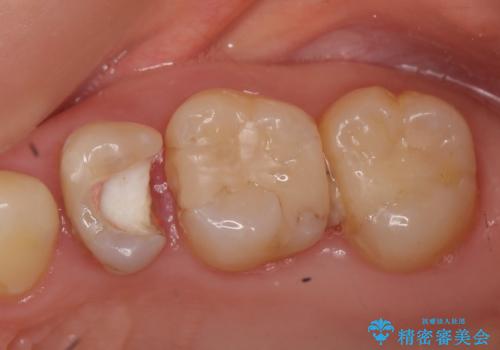

- 他院にて左上5番目の歯の根管治療を行っていたが、痛みが引かないため当院にいらっしゃった方の症例です。

左上5は再根管治療を行い症状の緩解を確認後、オールセラミッククラウンによる補綴を行いました。

左上6、7番目の歯もしみるとのことだったので古い樹脂及び虫歯を除去後、オールセラミッククラウンによる補綴を行いました。

※右上5は歯肉縁下まで虫歯だったため歯冠長延長術を提案しましたが希望されませんでした。